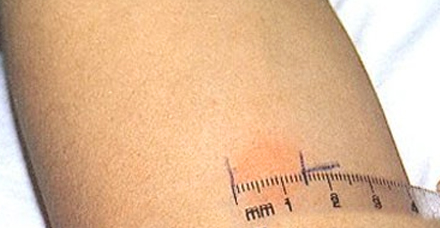

A Mantoux teszt során a legfontosabb az eredmény helyes mérése. Az injekció beadásának helyszíne gyakran vörösre vált és gyulladt, duzzanat és edzés jelentkezik. A teszt eredménye ebben az esetben csak a pecsét átmérője, a bőrpír nagysága semmilyen módon nem befolyásolja az eredményt, és egyéni reakció.

A papula átmérőjét csak egy merev átlátszó vonalzóval mérik, majd ezeket a méreteket összehasonlítják a normákkal:

• 0-1 mm - „negatív reakció”;

• 2-4 mm - „kétes reakció” (a gyermek a kockázati csoportba tartozik);

• 5 mm-től - „pozitív reakció” (a betegség nagy valószínűsége, de nem egyetlen Mantoux-teszttel diagnosztizálják őket, további vizsgálatok szükségesek);

• 17 mm-től - „hipererg reakció” (a betegség súlyos jele).